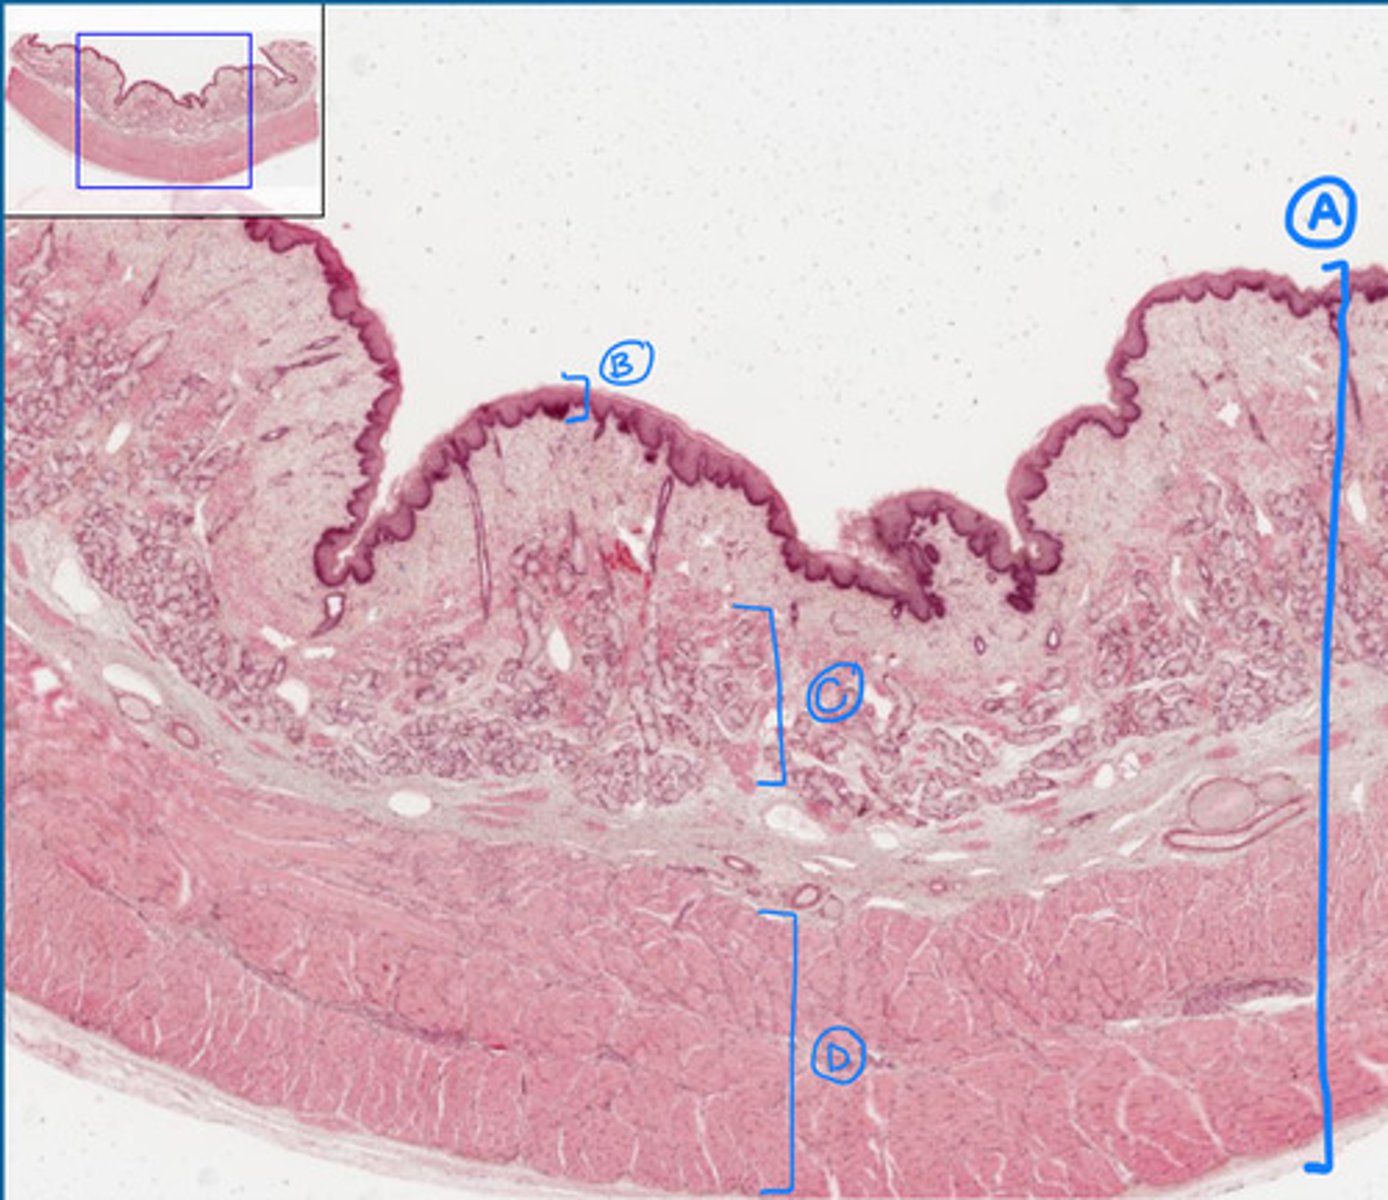

esophagus

A

mucosa of the esophagus

B

submucosa of the esophagus

C

muscularis of the esophagus

D